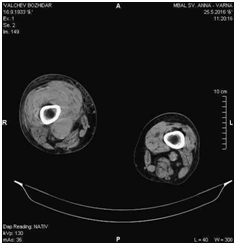

There were no significant blood test abnormalities, except elevated C-reactive protein. Electrolytes and renal function tests were normal. Performed color Doppler ultrasound of the lower leg vessels revealed an image with a greatest diameter of 38.32mm within the topography of the SFA, poorly-defined limits and mural thrombus. These characteristics suggested a ruptured aneurysm of the SFA (Figure 3). Computed tomography angiography (CTA) revealed ruptured aneurysm of right SFA with a diameter of 34mm (Figure 4 and 5).

Figure 3 Ruptured aneurysm of the SFA.

Figure 4 CTA image showing an aneurysm of the right SFA.

Figure 5 CTA image showing an ruptured aneurysm of the right SFA.